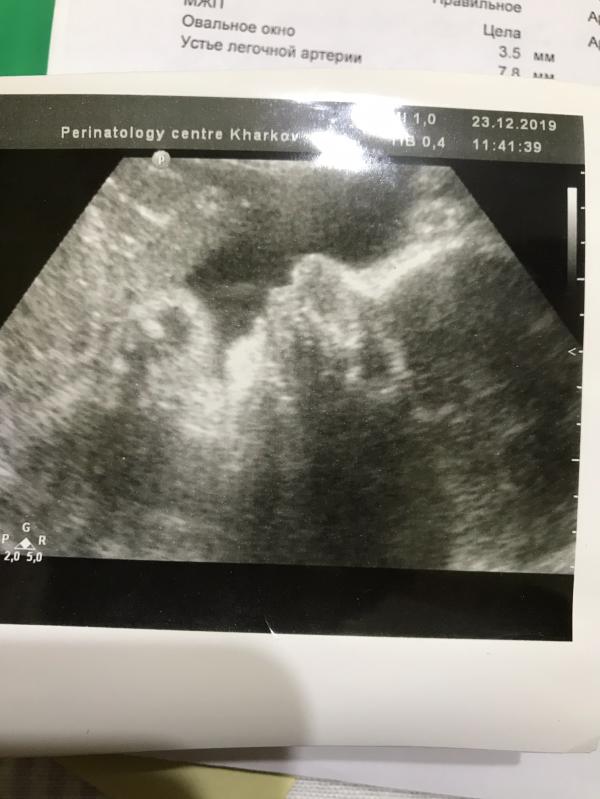

Здесь нашей девочке было 32 недели 🥺